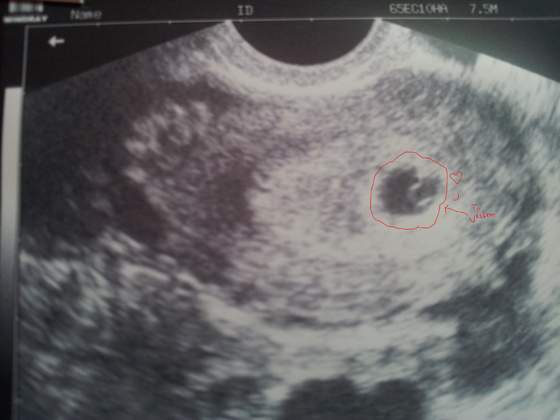

jak to nie wiele?!?! widac wszystko!!!! WIELKIE SZCZĘSCIE ;-))) POZDRAWIAMco prawda widać niewiele ale mogę pokazać pierwszą słiit fotkę heheZobacz załącznik 624721